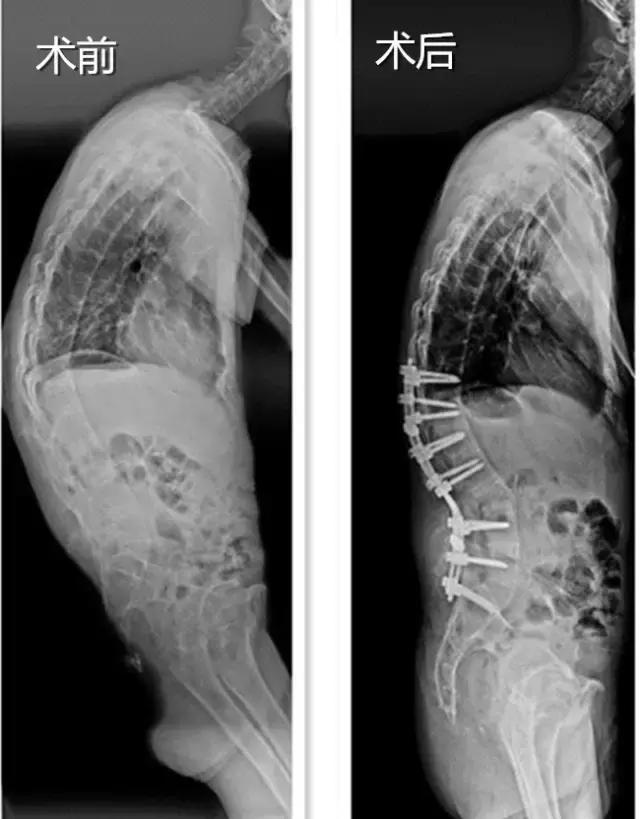

“李先生属比较严重的胸腰段强直性脊柱炎后凸畸形,这已经影响到了他的正常工作与生活,我们希望通过矫正手术来提高他的生活质量。”市中心医院脊柱外科主任黄庆华说,经过和李先生及家人充分沟通同意此治疗方案,手术团队即对他的病情进行了全科大讨论,决定为其实施矫形手术。

经过术前充分准备,李先生被送入手术室手术。医生在他弓起的脊柱部位切开了一个三十多厘米的口子,在脊柱的椎弓根上钉了两排各7颗的钛合金钉子,又在脊柱上截出一块倒三角形的骨头,合拢截面,弯曲的脊柱就被“拉直”了。

黄庆华主任说,这个手术最大的风险在于截骨的时候要避免伤及神经,否则患者有可能瘫痪,落下残疾。但是凭借市中心医院脊柱外科专家团队娴熟的手术技巧和密切合作,手术顺利完成,整个手术过程只用了3个多小时,术中出血仅600毫升左右。经过术后两个星期的康复治疗,李先生已经能佩戴支具下床行走,腰杆终于挺直了,走路再也不用“逢人哈腰”了。黄主任说,再过几个月,李先生基本上能正常生活了,对于一般的工作也能很好适应。